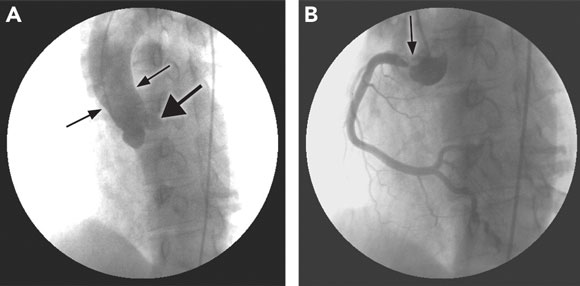

A coronary angiogram revealed a completely occluded left main coronary artery at the ostium, and a 90% ostial lesion of his right coronary artery; the remainder of his right coronary system was clear of disease (Figure 2). He underwent emergency coronary artery bypass grafting. The operative notes do not comment on the appearance of the native coronary arteries, nor were these sent for histological examination. An aortic wall biopsy showed mild degenerative changes only — syphilis could not be excluded as causing these changes. In view of the bilateral coronary ostial lesions, syphilis serology was performed.

2 Coronary angiograms of Patient 2 \

A: Tapering of the aortic root (thin arrows) and left main coronary stump (arrowhead). |